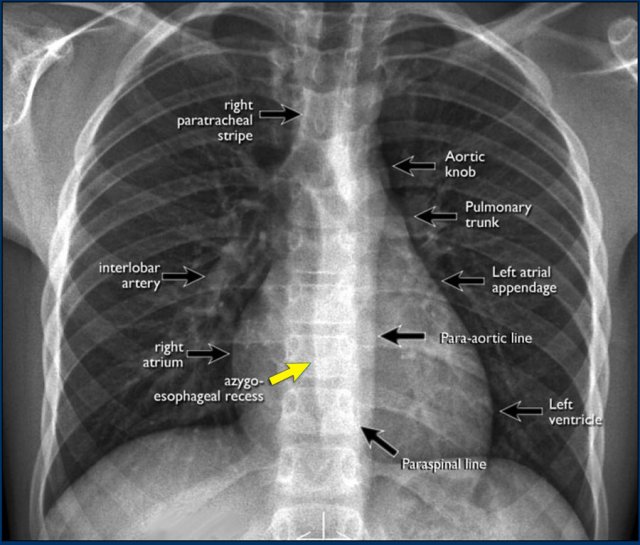

On the PA chest-film it is important to examine all the areas where the lung borders the diaphragm, the heart and other mediastinal structures.

At these borders lung-soft tissue interfaces are seen resulting in a:

- Line or stripe - for instance the right para tracheal stripe.

- Silhouette - for instance the normal silhouette of the aortic knob or left ventricle

These lines and silhouettes are useful localizers of disease, because they can be displaced or obscured with loss of the normal silhouette. This is called the silhouette sign, which we will discuss later.

The paraspinal line may be displaced by a paravertebral abscess, hemorrhage due to a fracture or extravertebral extension of a neoplasm.

Widening of the paratracheal line (> 2-3mm) may be due to lymphadenopathy, pleural thickening, hemorrhage or fluid overload and heart failure.

Displacement of the para-aortic line can be due to elongation of the aorta, aneurysm, dissection and rupture.

An important mediastinal-lung interface to look for is the azygoesophageal line or recess (arrow).

Azygo-esophageal recess

The azygo-esophageal recess is the region inferior to the level of the azygos vein arch in which the right lung forms an interface with the mediastinum between the heart anteriorly and vertebral column posteriorly.

It is bordered on the left side by the esophagus.

Deviation of the azygoesophageal line is caused by:

- Hiatal hernia

- Esophageal disease

- Left atrial enlargement

- Subcarinal lymphadenopathy

- Bronchogenic cyst